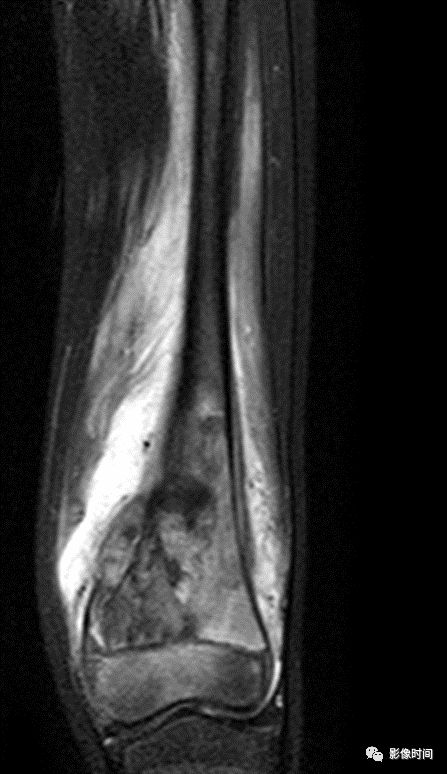

(三)浸润性破坏  浸润性骨破坏(图 9、图 10、图 11)是肿瘤组织沿哈弗氏管呈浸润性生长侵蚀骨与骨髓的结果。往往是分化很差、高度间变、异型性明显的肿瘤组织对骨的侵蚀。

影像学表现为筛孔样、虫蚀样(皮质骨)、渗透样、斑片状(松质骨)和大片溶骨性破坏,其破坏特点是肿瘤边缘模糊,境界不清,与正常骨无明显界限且有融合成片的倾向。

这种不同形态的骨破坏主要是肿瘤对骨侵蚀的程度和部位不同所决定的,不能作为肿瘤定性诊断的依据。

图 9  浸润性破坏:骨肉瘤

图 10  浸润性破坏:未分化多形性肉瘤

图 11  浸润性破坏:骨淋巴瘤